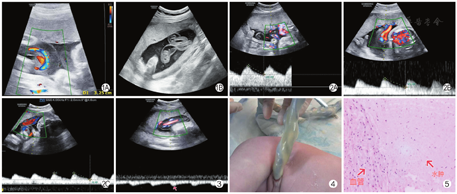

孕妇,27岁,孕5产1。孕27+1周自觉腹部胀痛来承德市中心医院就诊。行胎儿超声检查:单胎头位,脊柱连续,双顶径70 mm,头围243 mm,腹围235 mm,股骨长47 mm,胎儿心率140次/min,规律,羊水指数7.37 cm,内透声好,胎盘位于子宫前壁,厚度29 mm,Ⅰ级,胎儿胸腔及腹腔各脏器及肢体均未见明确异常,羊水中见脐带漂浮,横断面呈"品"字形结构,发现脐带局部增宽,最宽处约32.5 mm(图1),脐血管周围有宽约16 mm的液性无回声区,脐动脉阻力指数(resistance index,RI)0.41,收缩期峰值血流速度/舒张末期血流速度(systolic/diastolic,S/D)1.70,加速时间(acceleration time,AT)84 ms(图2A),胎儿皮肤未见明显水肿征象。考虑胎儿脐带回声异常,脐带水肿可能。孕27+5周出现劳累后阵发下腹痛,超声检查提示:脐动脉RI 0.51,S/D 2.02,AT 66 ms(图2B),余与第一次检查变化不大,考虑脐带水肿。孕28+1周复查超声提示:胎儿颈部可见脐带压迹,呈"U"形,脐带迂曲反折,脐血管周围可见液性无回声区,最宽处约35 mm,脐动脉RI 0.57,S/D 2.31,AT 86 ms(图2C),另外在脐带水肿明显处测及AT延长的小慢波,表现为RI降低、AT延长、收缩期波峰消失,呈低速低搏动性频谱(图3)。超声诊断:①晚期妊娠,单胎,头位,左枕前位;②胎儿脐带绕颈1周;③胎儿脐带回声异常,脐动脉血流频谱异常,考虑脐带水肿伴脐血流受阻可能。孕28+2周患者出现腹部紧缩感,伴轻微下腹痛及腰痛,腹痛逐渐加重,随后顺产一男婴,体重1 150 g,Apgar评分1 min 1分,5 min 2分,10 min 9分,入新生儿监护室。胎儿脐带娩出后见脐带局部增粗,明显肿胀,颜色稍苍白,呈半透明状。经测量:脐带总长度62 cm,无水肿处平均直径1.5 cm,局部水肿处长度14 cm,平均直径3.5 cm(图4)。产后脐带病理报告示:脐血管3根,水肿液积聚于脐带间质纤维结缔组织内,颜色淡染,局部伴黏液变性(图5)。